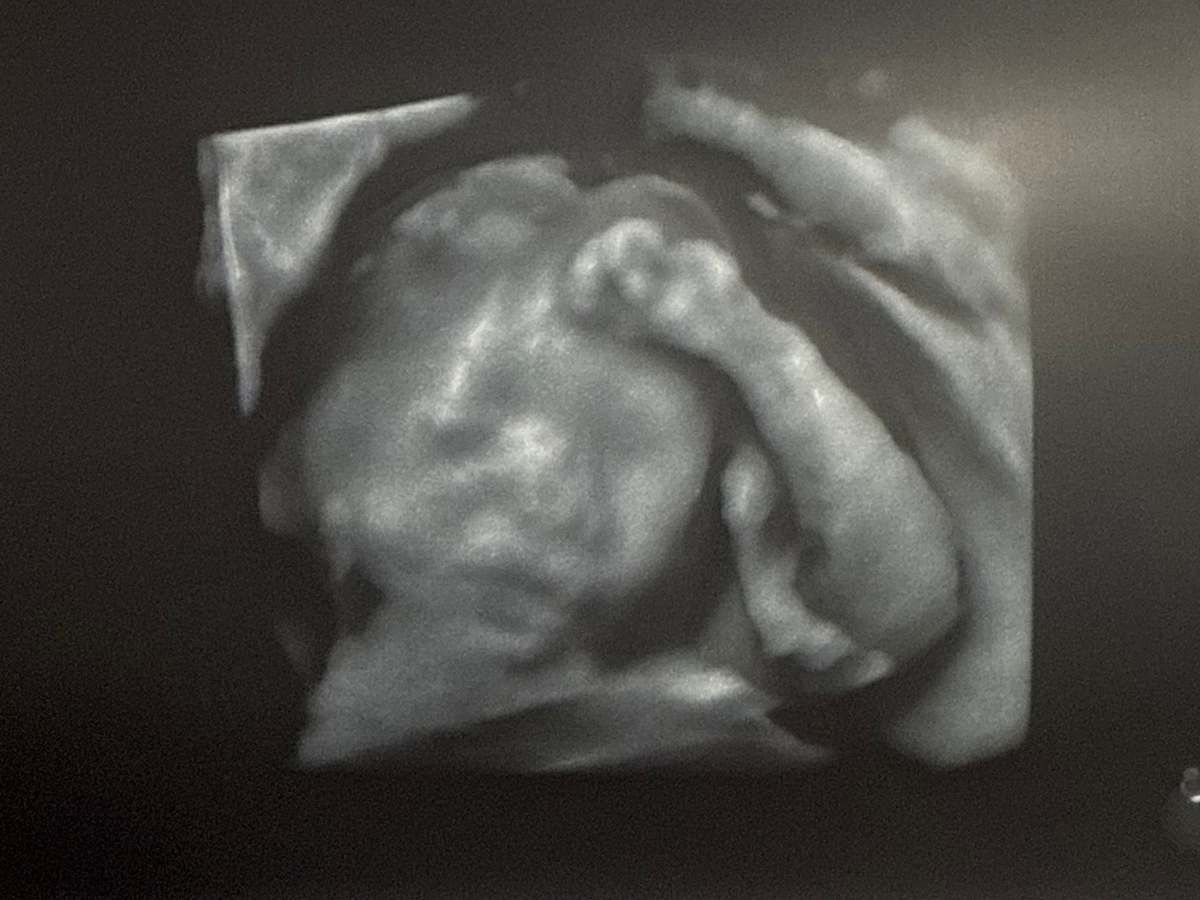

Main fundraiser photo

Hi, my name is Lindsey. My boyfriend, Jeremiah, and I are so glad to be welcoming a baby boy into this world. We are raising money to cover unexpected medical expenses for our baby boy. During our 20-week anatomy scan, the scan showed a hole in the baby’s diaphragm. This condition is called Congenital Diaphragmatic Hernia. This is causing our baby’s stomach to enter the chest cavity. Because of this, his lungs are not developing. Our high-risk doctor recommends we get a procedure done while he’s still in utero. This procedure will take place in Texas. With this procedure, we will have to stay near the hospital in case labor were to occur unexpectedly. Please help us raise funds for living and travel expenses while we will be away from work during these times. We appreciate all donations, no matter the size. Thank you for all your love and support during these hard times!